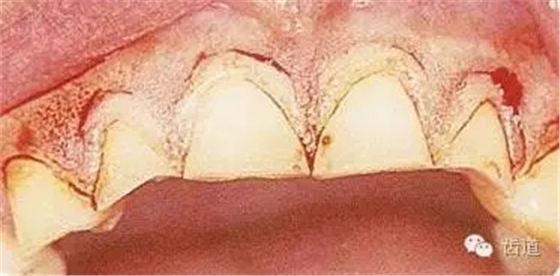

在臨床上,當(dāng)牙冠折斷或齲壞達(dá)齦下時(shí),會(huì)影響修復(fù)體的制作,常常因此而導(dǎo)致拔牙,如此時(shí)能將臨床牙冠延長(zhǎng),則會(huì)為制作良好的修復(fù)體創(chuàng)造條件,從而避免拔牙。臨床方法即為牙冠延長(zhǎng)術(shù)。

牙冠延長(zhǎng)術(shù)是通過(guò)手術(shù)方法,降低牙齦緣位置、暴露健康的牙齒結(jié)構(gòu),使臨床牙冠加長(zhǎng),從而利于牙齒的修復(fù)或解決美觀問(wèn)題。

牙冠延長(zhǎng)術(shù)的原理是基于牙齦的生物學(xué)寬度。通常將齦溝底與牙槽嵴頂之間的恒定距離稱(chēng)為生物學(xué)寬度,約為圓援 園源 皂皂,它的建立與穩(wěn)定是保證牙周組織健康的關(guān)鍵。單純的牙齦切除術(shù)只是把增生覆蓋于牙根斷面上的牙齦去除了,但不能恢復(fù)生物學(xué)寬度中的骨嵴頂上方的結(jié)締組織和結(jié)合上皮的附著位置,冠修復(fù)后如果冠邊緣侵犯了生物學(xué)寬度,作為一種保護(hù)機(jī)制,機(jī)體以骨吸收和牙齦增生的方式試圖重建,這樣將會(huì)導(dǎo)致慢性炎癥的長(zhǎng)期存在。牙冠延長(zhǎng)術(shù)通過(guò)手術(shù)的,降低齦緣的位置,去除相應(yīng)的牙槽骨,延長(zhǎng)過(guò)短的臨床牙冠,有利于修復(fù)或解決前牙美觀問(wèn)題。